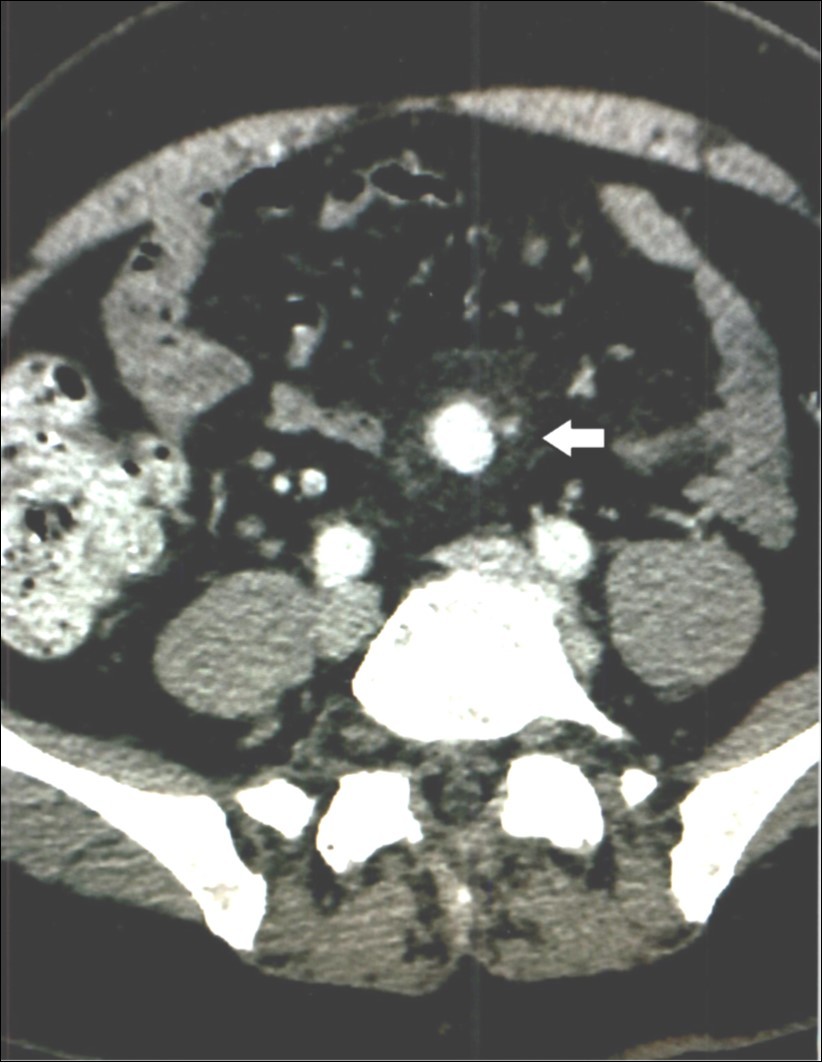

Complete metabolic panel was normal with normal hemogram. Immediate computed tomography (CT scan) revealed a 1.5 x 2 centimeter mesenteric aneurysm, possibly ruptured, Figure 2, as well as two smaller aneurysms a few millimeters each in diameter and abdominal aortic and carotid dilatation. A few small galls stones were seen. Immediate percutaneous embolization of the large aneurysm was performed two days before the procedure and six days afterward he received Levaquin. Follow up CT scan of the abdomen 18 months later showed the embolized mesenteric aneurysm and no change in the smaller ones. The symptoms have not recurred two years later.

Figure 2.Case 2 – Superior Mesenteric Artery Branch Aneurysm.

In our second patient, Case 2, in addition to the aneurysm, the CT scan indicated “probable” bleeding, Figure 2, without any sign of systemic bleeding or infection, clinically or in the hemogram. The blood cultures were normal six days after treatment. White blood cell counts were normal and only mild anemia was present. Therefore, it is doubtful the aneurysm was mycotic. The “halo” around the aneurysm can be interpreted as pressure effect of the enlarging aneurysm on the surrounding tissues.